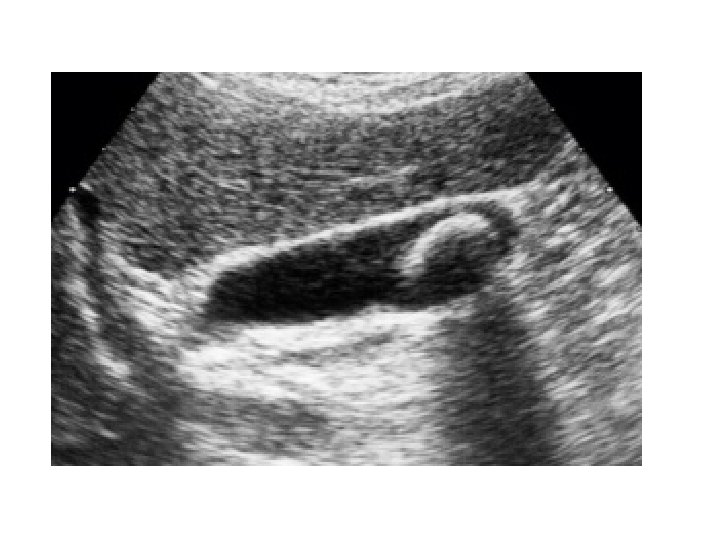

Gallstones • Hyperechoic area casting a posterior acoustic shadow. • Risk factors : obesity, drugs, ileal diseases, ileal resection, parasitic infection(ascariasis) • Cholesterol, Pigment and Mixed gall stones • Cholecystectomy